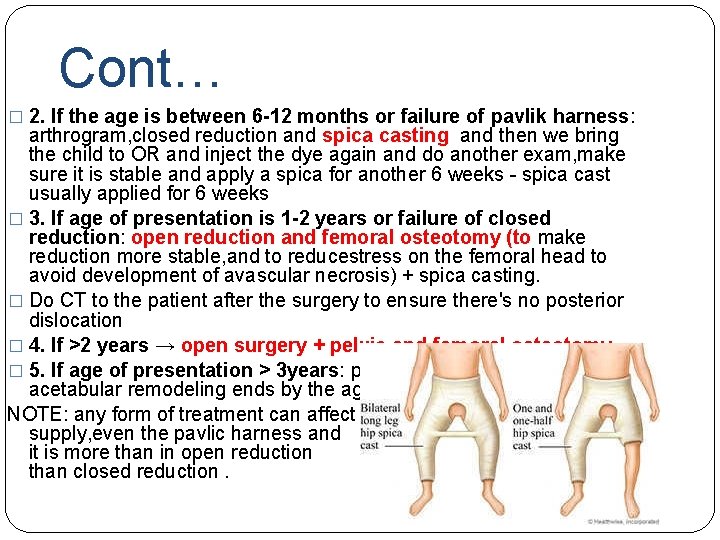

Cont… � 2. If the age is between 6 -12 months or failure of pavlik harness: arthrogram, closed reduction and spica casting and then we bring the child to OR and inject the dye again and do another exam, make sure it is stable and apply a spica for another 6 weeks - spica cast usually applied for 6 weeks � 3. If age of presentation is 1 -2 years or failure of closed reduction: open reduction and femoral osteotomy (to make reduction more stable, and to reducestress on the femoral head to avoid development of avascular necrosis) + spica casting. � Do CT to the patient after the surgery to ensure there's no posterior dislocation � 4. If >2 years → open surgery + pelvic and femoral osteotomy � 5. If age of presentation > 3 years: palliative surgery because acetabular remodeling ends by the age of 3. NOTE: any form of treatment can affect blood supply, even the pavlic harness and it is more than in open reduction than closed reduction.